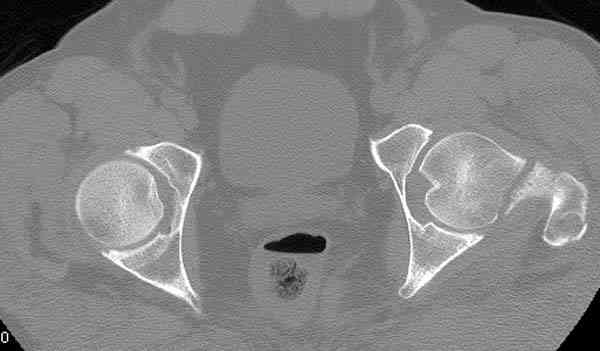

Кроме обязательных ренгенологических снимков тазобедренного сустава, при подозрении на перелом шейки рекомендуем Компьютерную Томографию.

Года два назад в ОТА из группы Торнетта было доложено о "missed femoral neck fractures" даже после КТ исследования.

Здесь представлены снимки больного 65 лет, поступившего с диагнозом перелом

бедра после автоаварии.

На второй день (7) обнаружен пропущенный перелом,

сделаны Компьютерная Томограмма